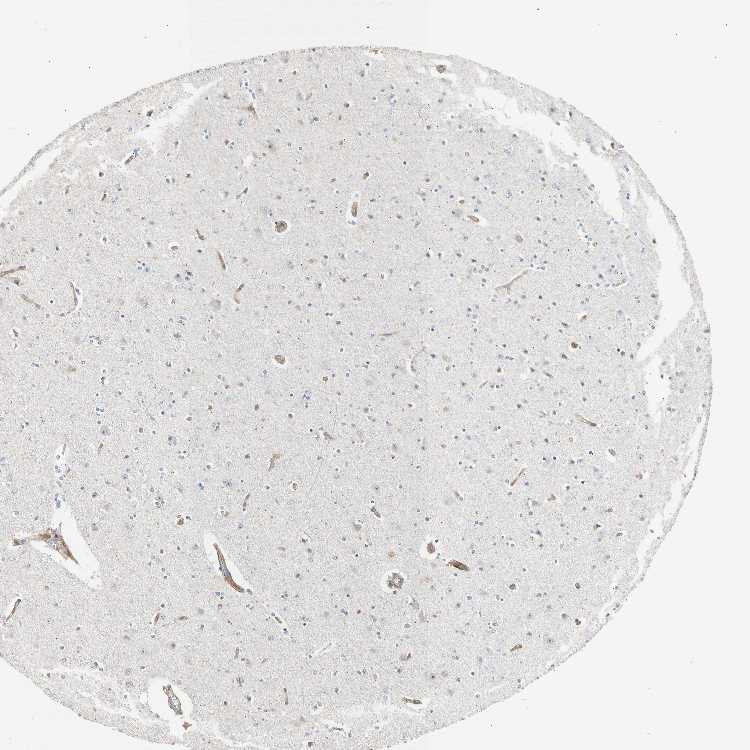

CEREBRAL CORTEX - Antibody stainingi

Antibody staining in the annotated cell types in the current human tissue is reported as not detected, low, medium, or high, based on conventional immunohistochemistry profiling in selected tissues. This score is based on the combination of the staining intensity and fraction of stained cells.

Each image is clickable and will lead to virtual microscopy that enables deeper exploration of all samples and also displays staining intensity scores, fraction scores and subcellular localization as well as patient and tissue information for each sample.

Antibody HPA008025

Endothelial cells Medium

Glial cells Not detected

Neuronal cells Not detected

Neuropil Not detected